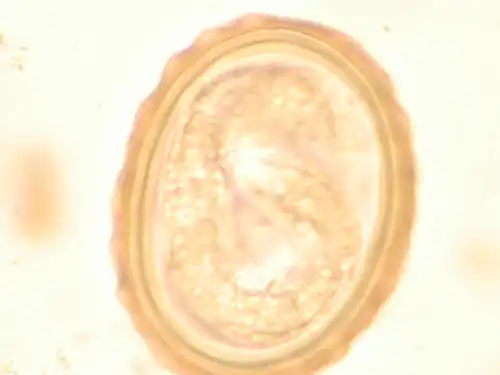

The larva of Ascaris lumbricoides developing in the egg -

Most diagnoses are made by identifying the appearance of the worm or eggs in feces. Due to the large quantity of eggs laid, diagnosis can generally be made using only one or two fecal smears.[33] The diagnosis is usually incidental when the host passes a worm in the stool or vomit. The eggs can be seen in a smear of fresh feces examined on a glass slide under a microscope and there are various techniques to concentrate them first or increase their visibility, such as the ether sedimentation method or the Kato technique. The eggs have a characteristic shape: they are oval with a thick, mamillated shell (covered with rounded mounds or lumps), measuring 35–50 micrometer in diameter and 40–70 in length. During pulmonary disease, larvae may be found in fluids aspirated from the lungs. White blood cell counts may demonstrate peripheral eosinophilia; this is common in many parasitic infections and is not specific to ascariasis. On X-ray, 15–35 cm long filling defects, sometimes with a whirled appearance (bolus of worms).